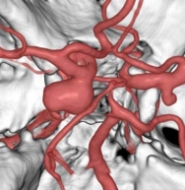

治療後

物が二重に見えるようになって発症した内頚動脈大型動脈瘤(矢印)の症例です。クリッピング術で直接動脈瘤をつぶすことができないため、バイパス術(矢印)を増設し内頚動脈を遮断することで動脈瘤を治療しました。